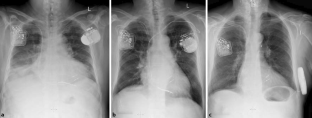

Abb. 1

Abb. 2

Abb. 3

Abb. 4

Abb. 5

Abb. 6